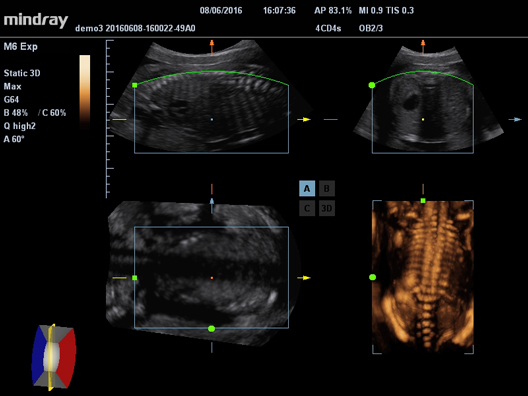

УЗ-сканер Mindray М6 exp представляет собой полнофункциональную портативную, размером с ноутбук, систему цветной допплерографии. Аппарат обеспечивает безупречную визуализацию в формате 2D. Оснащенная специализированными технологиями система М6 exp является оптимальным вариантом для применения.

Галерея изображений